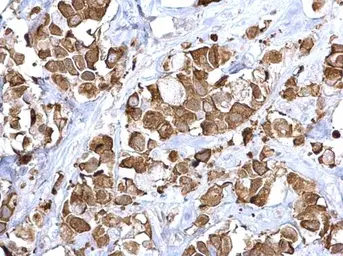

Anti-Fatty Acid Synthase antibody [N1], N-term used in IHC (Paraffin sections) (IHC-P). GTX109833

Fatty Acid Synthase antibody [N1], N-term detects Fatty Acid Synthase protein at cytoplasm on human breast carcinoma by immunohistochemical analysis.

Sample: Paraffin-embedded human breast carcinoma.

Fatty Acid Synthase antibody [N1], N-term (GTX109833) diluted at 1:500.

Antigen Retrieval: Trilogy™ (EDTA based, pH 8.0) buffer, 15min